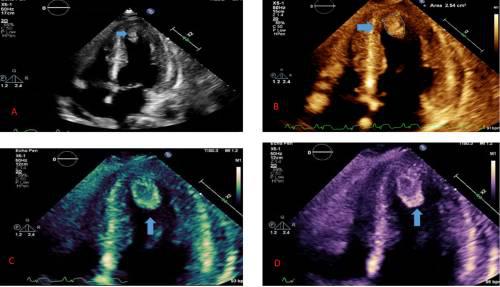

术后超声心动图显示左心室射血分数(LVEF)30%,心尖部、外侧壁运动严重减退、左心室回声密度(2.4 cm×1 cm)与血栓相似(图3)。

图3